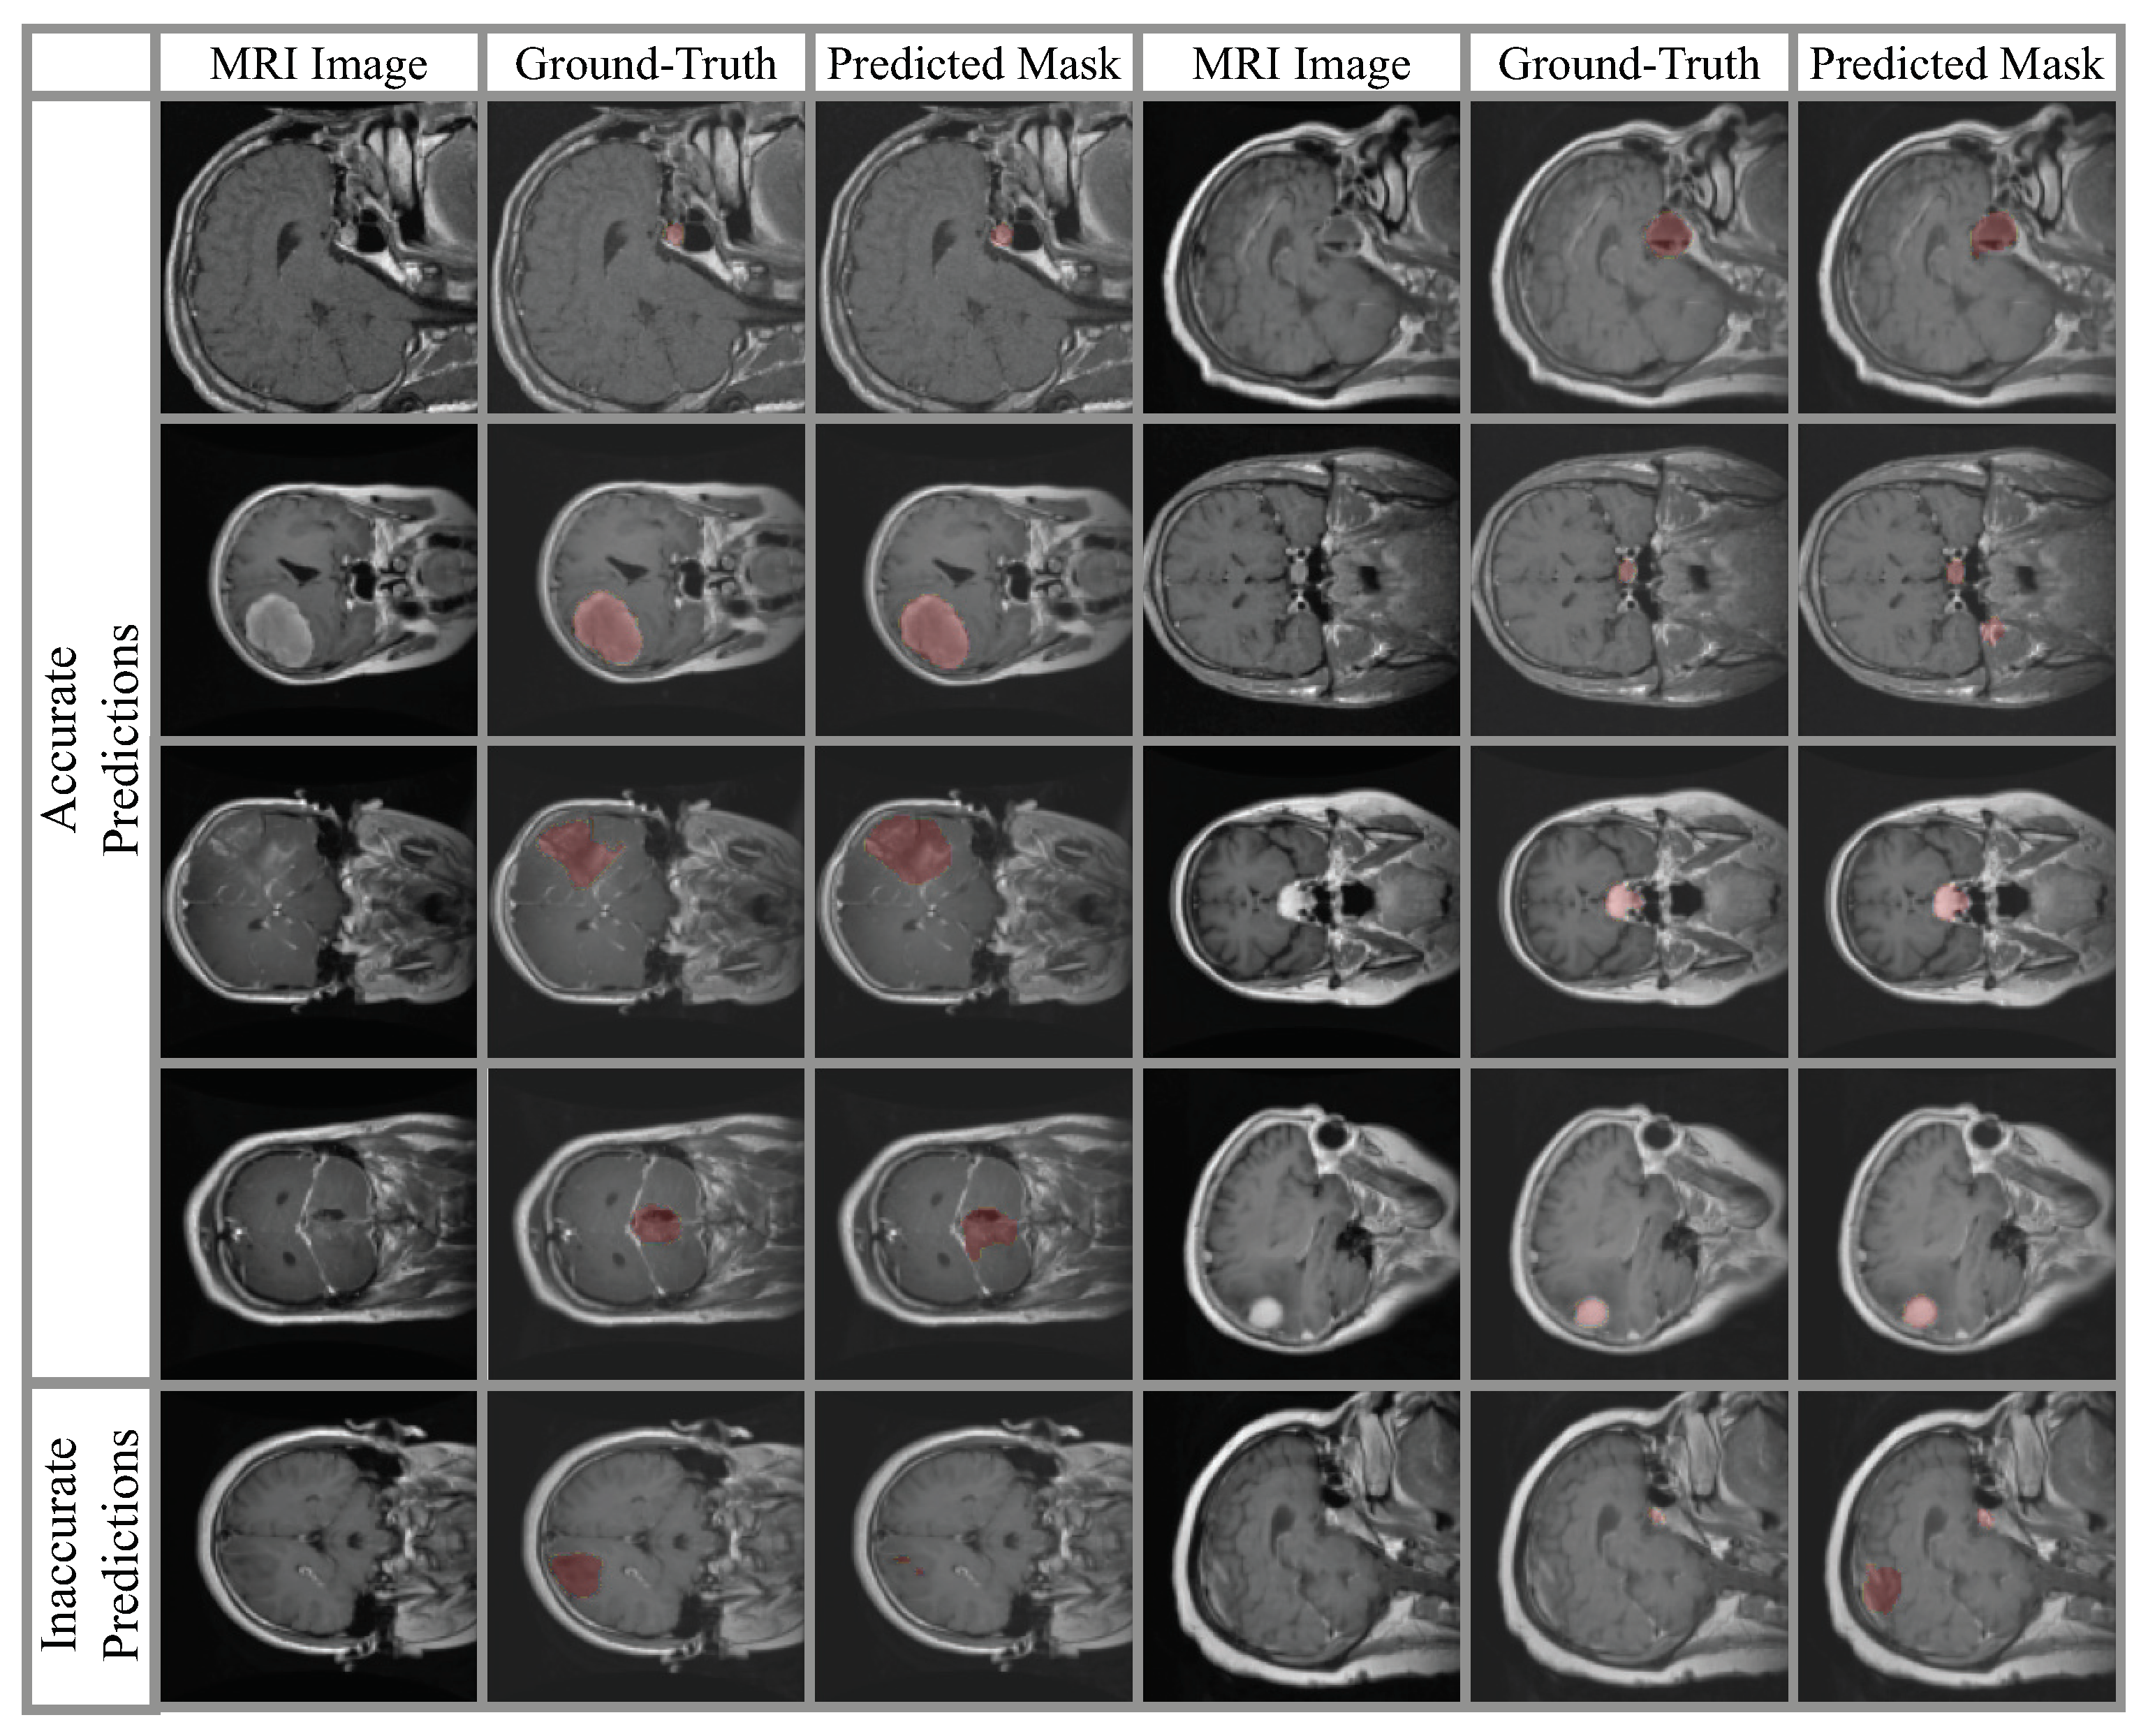

4. Experimental Results

4.2. Classification Results